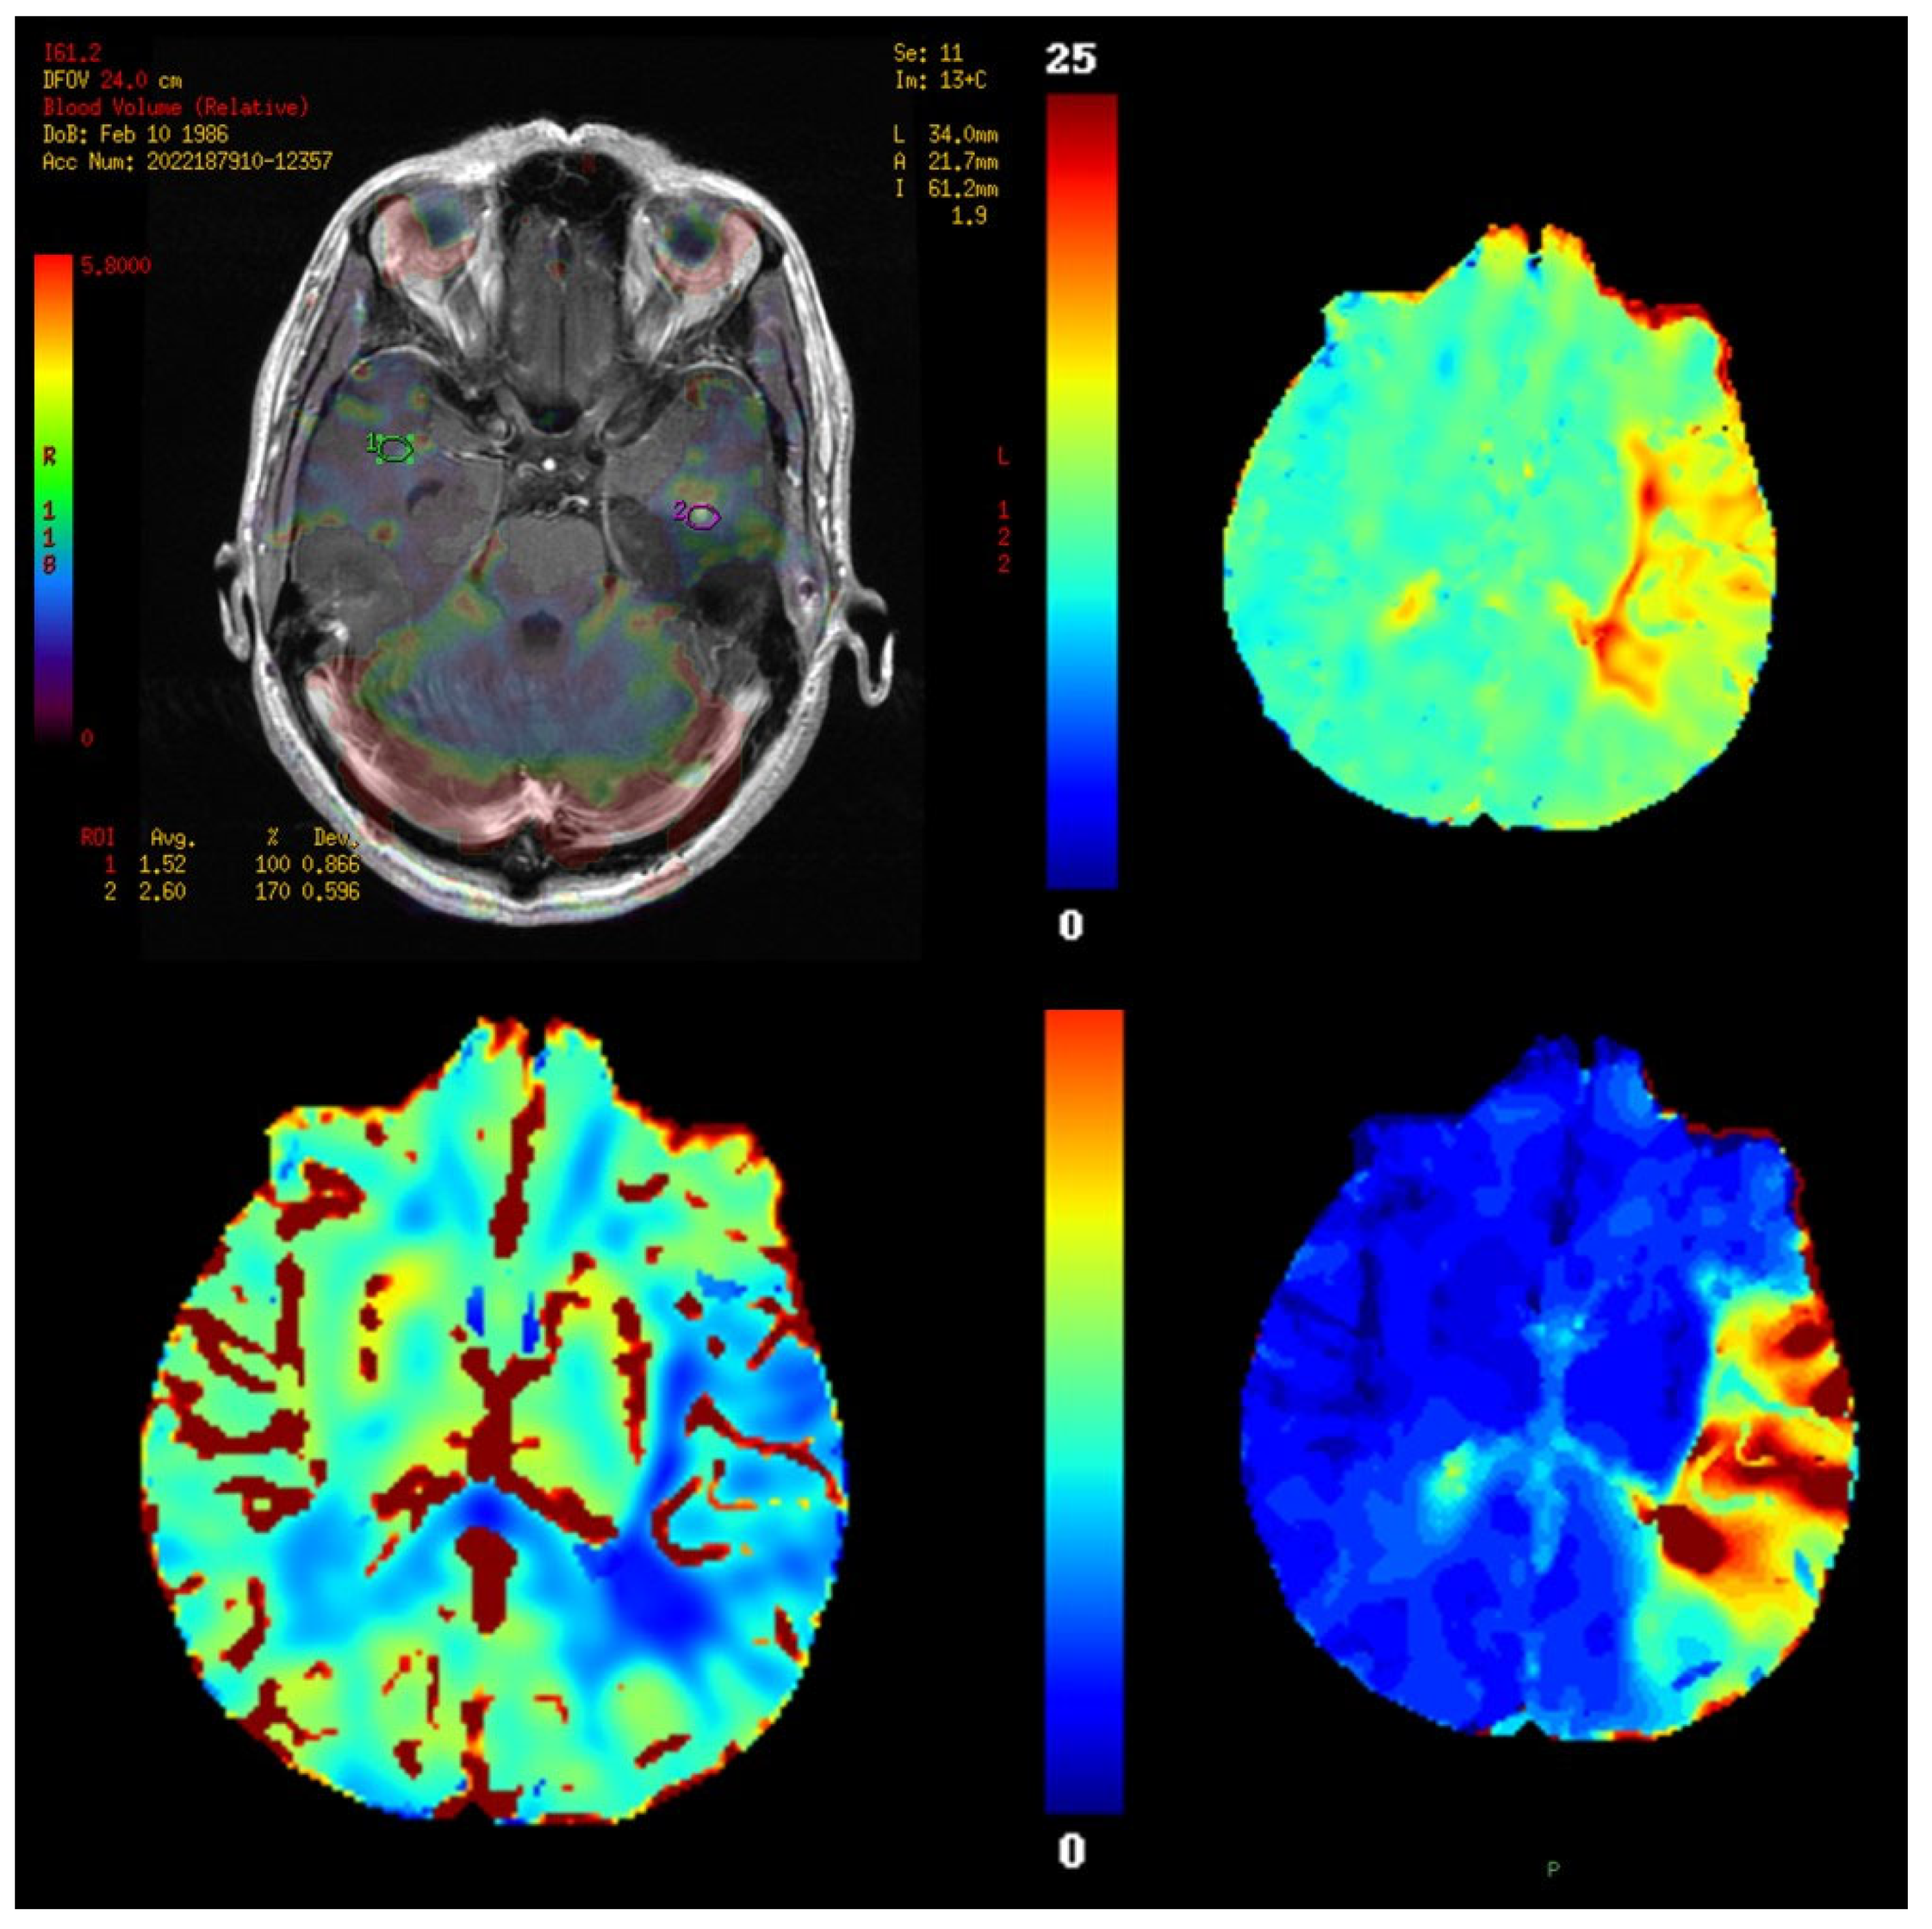

11. Perfusion Imaging

11.1. Physics and Signal Model

11.3. Outputs and Units

11.4. Validation and Quantification Considerations

11.5. Clinical Applications

- Tumor grading and characterization,

- Eilaghi, A.; Yeung, T.; D’Esterre, C.; Bauman, G.; Yartsev, S.; Easaw, J.; Fainardi, E.; Lee, T.-Y.; Frayne, R. Quantitative Perfusion and Permeability Biomarkers in Brain Cancer from Tomographic CT and MR Images. Biomarkers Cancer 2016, 8s2, BIC.S31801–BIC.S31859. [Google Scholar] [CrossRef] [PubMed]

- Boxerman, J.; Schmainda, K.; Weisskoff, R. Relative Cerebral Blood Volume Maps Corrected for Contrast Agent Extravasation Significantly Correlate with Glioma Tumor Grade, Whereas Uncorrected Maps Do Not. Am. J. Neuroradiol. 2006, 27, 859–867. [Google Scholar]

- Lupo, J.M.; Cha, S.; Chang, S.M.; Nelson, S.J. Dynamic Susceptibility-Weighted Perfusion Imaging of High-Grade Gliomas: Characterization of Spatial Heterogeneity. Am. J. Neuroradiol. 2005, 26, 1446–1454. [Google Scholar]

- Law, M.; Young, R.J.; Babb, J.S.; Peccerelli, N.; Chheang, S.; Gruber, M.L.; Miller, D.C.; Golfinos, J.G.; Zagzag, D.; Johnson, G. Gliomas: Predicting Time to Progression or Survival with Cerebral Blood Volume Measurements at Dynamic Susceptibility-weighted Contrast-enhanced Perfusion MR Imaging. Radiology 2008, 247, 490–498. [Google Scholar] [CrossRef]